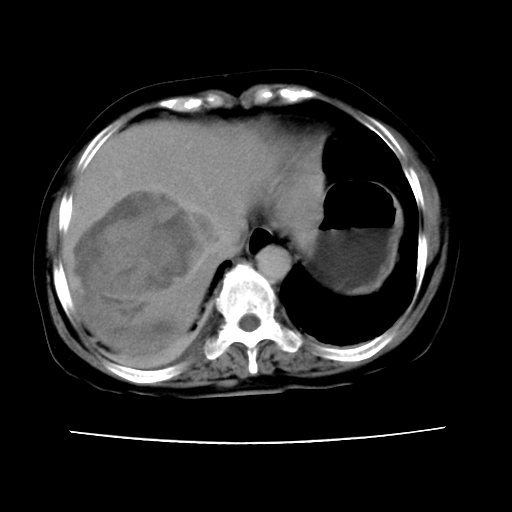

2008-11-10ct平扫(其间去中山医院诊治未行特殊治疗)

2008-11-10ct平扫见并肝内、血膜下血肿基本吸收,肝内低密度灶缩小。此时再做增强ct应有显着意义。对患者/医者都好!

从平扫+增强及治疗后复查片,病变明显缩小,不考虑肝癌出血可能,还是考虑为良性病变可能性大;单纯血肿并包膜下积液吧,病变强化没法解释,肝血管破裂出血吧,增强不符合典型血管瘤的表现,良性肿瘤破裂出血吧,复查片看来好像也不太支持(没做强化也不太好说)。本人还是考虑单纯肝内血肿并包膜下积液,强化是不是血管有外渗。

患者自6月至11月,如果是肝癌,没有经过特殊治疗,想必应该会有所进展吧,而不是ct所见,反而似有病灶减小的趋势。建议增强。